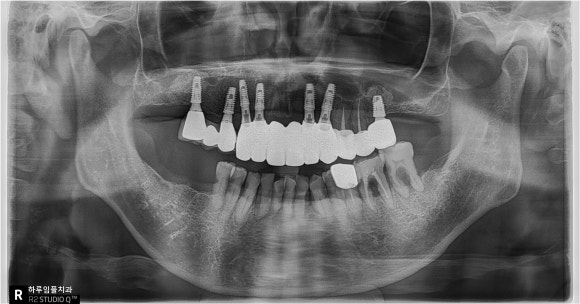

그날 바로

발치 12개임플란트 8개 식립

한 번에 진행했습니다.

이 과정은 속도싸움이 아니라

각도·깊이·초기 고정력

모두 고려해야 하는

고난도 수술이였습니다.

뼈 상태와 고정력이 안정적으로 나와

다음날 임시치아

바로 장착하기로 결정했습니다.